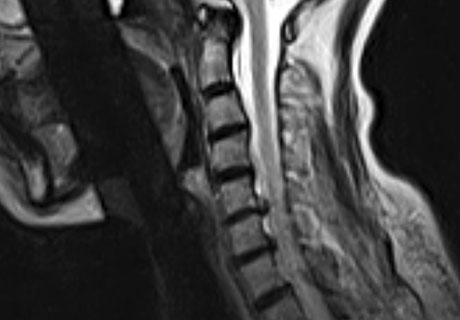

척수라는 중추 신경은 목뼈를 통과해 목 아래 감각과 운동 신경에 영향을 끼치기 때문에 목 디스크 증상들이 나타나면 신속하고 빠른 대처가 필요해요. 목디스크 치료형식으로 주로 초기 스탭에는 물리치료나 약물을 통해 대개의 환자들이 호전돼요. 그렇지 않다고 하면 신경 성형술과 차단술이라고 부르는 뼈주사 목디스크 치료방법을 이용하는데, 이 치료방법은 통증이 있는 신경 부위에 약물을 삽입하는 것입니다.

시술로써 눈에 띄게 질환을 현저히 치료하시는 것이 아니라 염증을 보완하고 통증을 낮추는 것이 포인트입니다. 이러한 방식으로 비 수술적인 치료를 3개월 이상 넘었음에도 불구하며 증상이 호전을 보이지 않으신다면 목디스크 치료방법 중 수술적 치료를 고심해야 하더라고요. 인공디스크를 투입하기 위함으로 절개를 통하기에 디스크를 제거하며 뼈를 하나로 유합 시켜서하는 것과, 내시경 수술로 빠져 나온 수핵 자체만을 제거시켜서하는 방법이 있다고하고요.

수술 방법에도 많은가 있다고 하는데 개괄적으로 설명을 하면 목을 절개해 망가진 디스크를 제거한 뒤 뼈를 하나로 유합하는 방법, 인공 디스크 투입술, 내시경을 활용해 바깥으로 빠져나온 수핵을 없애는 수술법 등이 있다고 합니다.